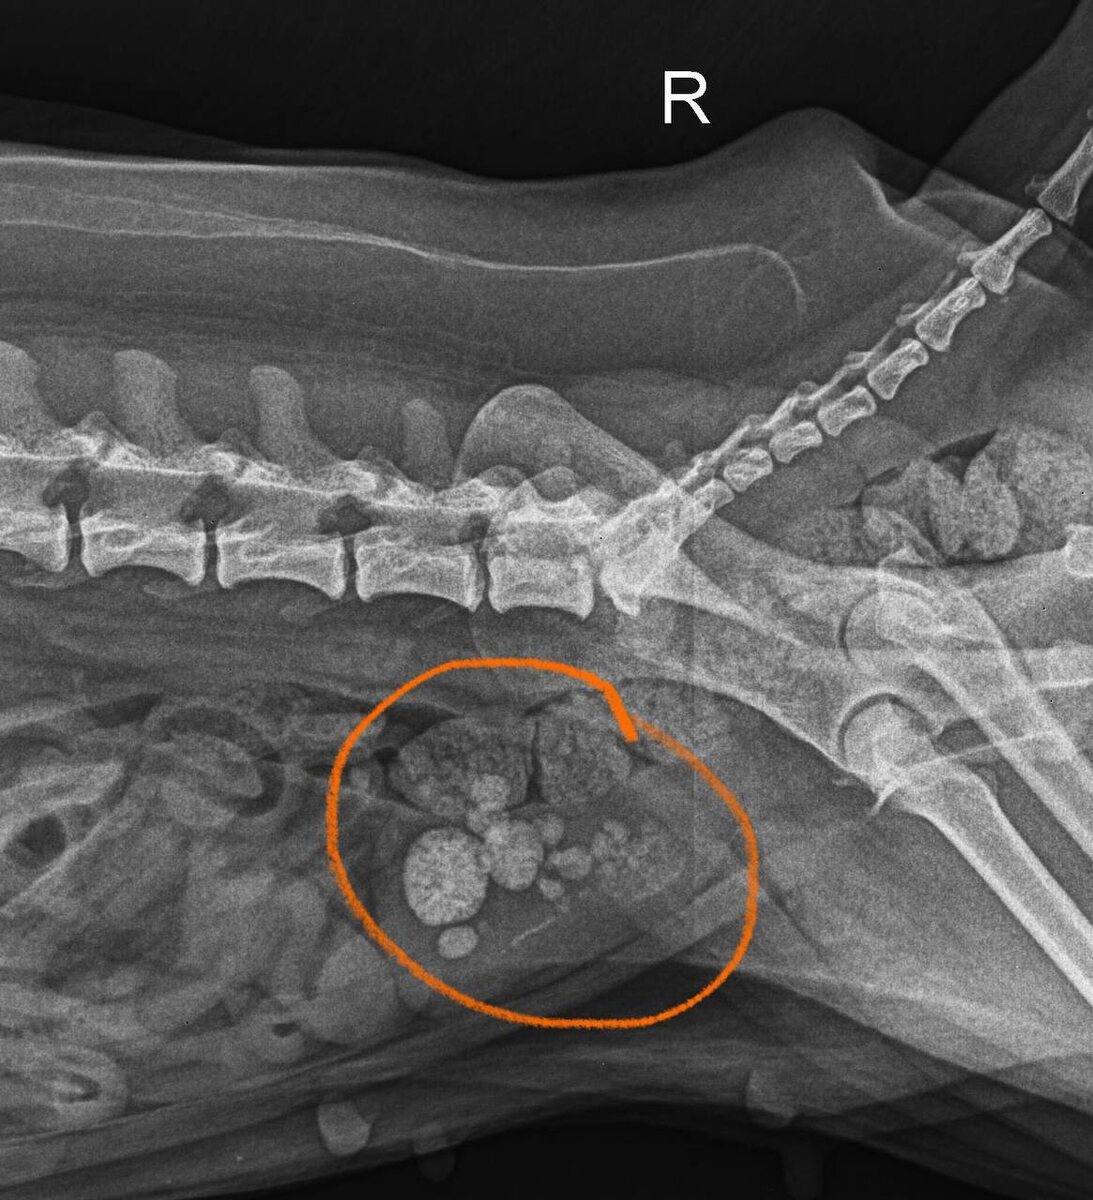

Пациенту Боника была проведена операция по удалению камней из мочевого пузыря.

🔸Хирург: Андреева Мария Александровна